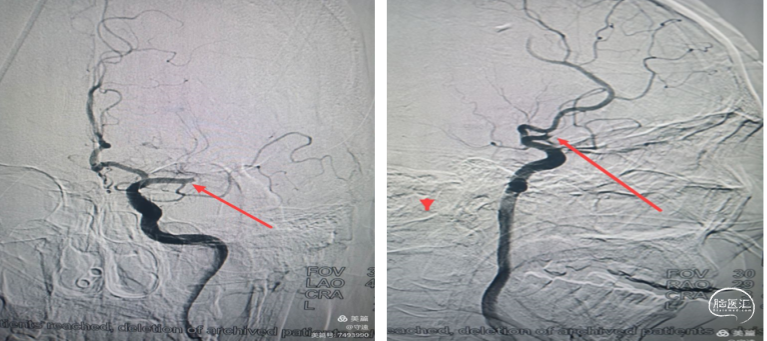

局麻下行血管内治疗:行右侧股动脉穿刺,脑血管造影真实左侧大脑中动脉M1段闭塞。血管断面呈“刀切征”or“截断征”。大脑前动脉部分代偿。

手术过程:银蛇070中间导管到达M1段直接抽吸。

裸奔:由于颈内血管路途迂曲不明显,路图下银蛇070中间导管“裸奔”到达M1段接触血栓部位。

踹马桶抽吸: “猛抽”将血栓吸入导管,进行快速踹、踹、踹马桶,注射器无回血,边踹负压抽吸,撤出体外,检查中间导管和注射器抽出2块红色血栓,冒烟观察血管再通。

抗血小板聚集:再次将微导管置于M1段起始部,给予替罗非班8mL,1mL/min推注。造影显示远端血流通畅。

2.脑血管造影示:右侧大脑中动脉M1以远末显示,副大脑中动脉有少量供血。M1段似有血栓影

3.取栓8F指引导管置于C1段,中天远端通路导管裸奔至M1段,导管尾部连接延长管,5OmL注射器"踹马桶"抽吸,无回血,负压下撤出体外,检查结果见约0.5cm大小白色血栓和少量点片状红色血栓。

4、快速二次接续抽吸:清理可能的残余血栓后造影右侧大脑中动脉血流通畅,未见明确血栓逃逸和狭窄。结束手术。